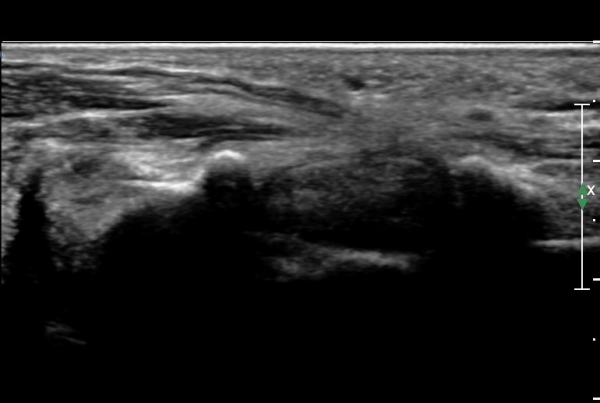

¼Õ¸ñ ºÎÀ§¿¡¼ Á¤Á߽Űæ Ⱦ´Ü¸é°Ë»ç»ó Á¤Á߽ŰÜÀÇ Àú¿¡ÄÚ ºÎÁ¾ÀÌ °üÂûµÊ(»çÁø 1).